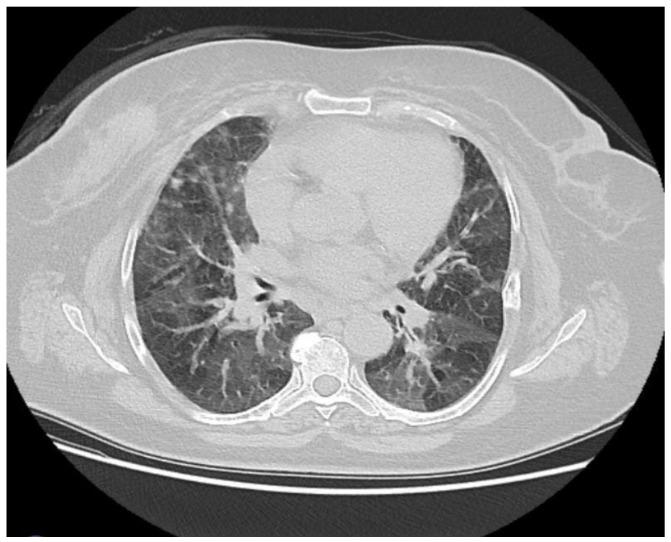

CDK4/6 inhibitors (CDK4/6i) have revolutionized the treatment of hormone receptor-positive HER2 negative (HR(+)/HER2(-)) breast cancer. Despite their efficacy, interstitial lung disease (ILD) remains a rare but potentially fatal adverse effect. This study aims to evaluate the incidence and clinical characteristics of ILD associated with CDK4/6 inhibitors in breast cancer patients in Turkey. : A retrospective multicenter analysis included 464 breast cancer patients treated with CDK4/6 inhibitors between January 2017 and April 2024. Patients receiving ribociclib or palbociclib were evaluated for the development of ILD. Radiological assessments were performed to confirm ILD and exclude other conditions. Clinical characteristics, treatment regimens, and outcomes were analyzed. : ILD was identified in 10 patients (2.1%). The average age of the affected patients was 62.5 ± 9.85 years. Hypersensitivity pneumonitis and nonspecific interstitial pneumonia (NSIP) were the most common radiological patterns. Palbociclib was implicated in six cases, while ribociclib was associated with four cases. Grade 3 pulmonary toxicity was observed in eight patients, and Grade 4 toxicity in two patients. One patient who was on palbociclib died due to ILD. No significant correlation was found between ILD and age, smoking status, lung metastases, or prior thoracic radiotherapy. : The incidence of CDK4/6 inhibitor-associated ILD in Turkish breast cancer patients appears higher than previously reported in clinical trials. More robust, long-term studies are necessary to identify potential risk factors and mitigate ILD-related mortality.

细胞周期蛋白依赖性激酶4/6抑制剂(CDK4/6i)彻底改变了激素受体阳性、人表皮生长因子受体2阴性(HR(+)/HER2(-))乳腺癌的治疗方式。尽管其疗效显著,但间质性肺疾病(ILD)仍然是一种罕见但可能致命的不良反应。本研究旨在评估土耳其乳腺癌患者中与CDK4/6抑制剂相关的ILD的发生率和临床特征。:一项回顾性多中心分析纳入了2017年1月至2024年4月期间接受CDK4/6抑制剂治疗的464例乳腺癌患者。对接受瑞博西尼或哌柏西利治疗的患者进行ILD发生情况评估。进行影像学评估以确诊ILD并排除其他疾病。分析临床特征、治疗方案和结局。:10例患者(2.1%)被确诊为ILD。受影响患者的平均年龄为62.5±9.85岁。过敏性肺炎和非特异性间质性肺炎(NSIP)是最常见的影像学表现。哌柏西利涉及6例,而瑞博西尼与4例相关。8例患者出现3级肺部毒性,2例患者出现4级毒性。1例接受哌柏西利治疗的患者因ILD死亡。未发现ILD与年龄、吸烟状况、肺转移或既往胸部放疗之间存在显著相关性。:土耳其乳腺癌患者中与CDK4/6抑制剂相关的ILD发生率似乎高于先前临床试验报告的发生率。需要更有力的长期研究来确定潜在风险因素并降低与ILD相关的死亡率。